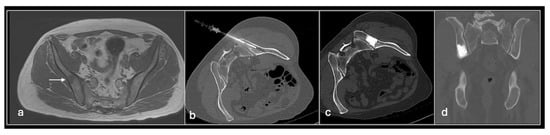

Figure 10. Axial T1 (a) showing metastasis in right ilium (arrow) (b) treated with radiofrequency ablation. Post-cementoplasty axial (c) and coronal (d) CT post-cementoplasty.

This technique is particularly used as a first-line curative option in osteoid osteomas and osteoblastomas. It is also effective in the cure of chondroblastoma [37,38]. As a palliative option, it has been used for painful bony and soft tissue metastases as well as myeloma and can be combined with cement augmentation to restore function [36,39,40].

Radiofrequency ablation uses temperatures of up to 95 °C applied over several minutes to induce tumour cell coagulation necrosis. Technically, this is achieved by positioning an RFA needle (the cathode) into the lesion using a similar approach to a bone biopsy (i.e., with a coaxial biopsy needle system including a drill) and applying a grounding pad to the patient’s thigh (the anode). Most treated lesions are surrounded by cortical bone, thus insulating adjacent structures from the hot needle tip and effectively heating the tumour. Before introducing the RFA needle, a biopsy is typically taken to confirm the suspected diagnosis.

As well as bearing in mind the ‘standard’ complications associated with percutaneous procedures involving bone such as fracture, infection, pain, and injury to neurovascular structures, RFA also can cause thermal injuries perilesional soft tissue as well as significant skin burns at the needle and grounding pad sites. Techniques such as injection of fluid or CO2 to separate structures or thermal monitoring of adjacent tissues can minimise the risk of injury (Figure 6, Figure 7, Figure 8, Figure 9, Figure 10 and Figure 11).

3.5.2. Cement Augmentation

Cement augmentation is the injection of polymethylmethacrylate cement (PMMA) mixture into a bony defect to restore bony structural integrity and provide pain relief. The most common form is vertebroplasty in the context of vertebral compression fractures which—in the setting of oncology—include pathological fractures with underlying myeloma or metastases with resultant pain and disability refractory to conservative treatment. The procedure is also a useful adjunct following percutaneous ablation to restore structural integrity following bone destruction, particularly for larger lesions [33] (Figure 13 and Figure 14).